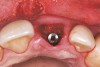

Figure 25  Case Three Titanium abutment seated

Figure 25

After placement of the graft complex, a titanium abutment with a 1-mm collar (Quick abutment, Keystone Dental) was seated and hand-tightened (Figure 25). Retrofitting of the natural tooth shell preserving the pre-existing contact point relationships and line-angle positioning was accomplished from a pretreatment incisal edge registration. The final provisional restoration can be seen in Figure 26.